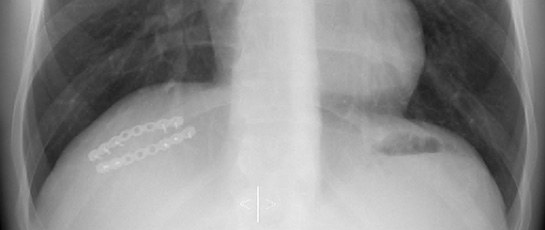

Surgery

Surgery remains an important option in treating rib, sternal or more complex chest wall injuries. The focus may be pain relief, or reconstruction of an abnormal area to its normal anatomy. Several types of operation are available and it's important that your surgeon is familiar with the different surgical options so that the type and severity of the chest wall problem can be treated with the best approach safely and effectively.